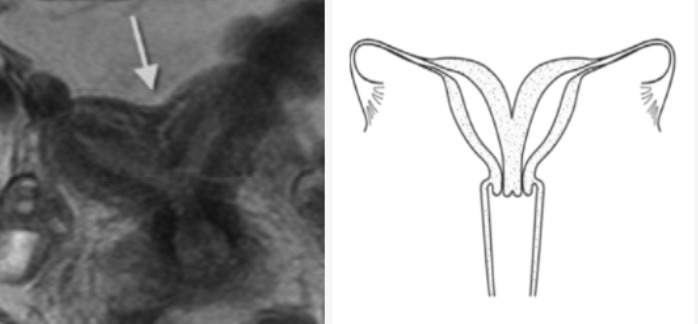

ÇİFT BOYNUZLU RAHİM (UTERUS BİKORNUS)

Bikornuat rahim (çift boynuzlu rahim), çift rahimden farklı bir şekil bozukluğudur. Rahmin tepe bölgesi, yani fundustan, 1 cm’den büyük bir girinti olması ve buna bağlı olarak tüplere açılan iki boynuzun orta hattaki devamlılığın olmaması durumudur.